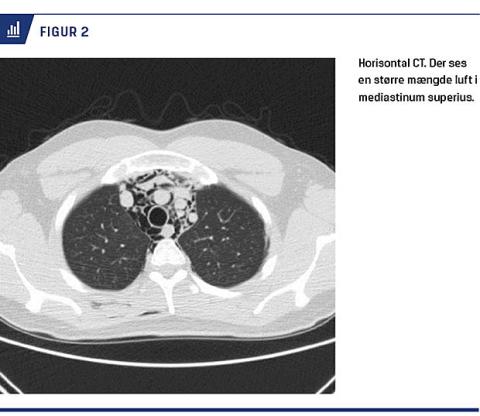

Hos børn er eleveret thymus et klassisk tegn. Hvis røntgenbilledet viser normale forhold, men der fortsat er klinisk mistanke om intratorakal patologi, anbefales CT af thorax. Her kan Macklineffekten, som defineres som ansamling af luft i den bronkovaskulære hinde og det omkringliggende væv, ses hos 100% af patienterne med SME. Hyppigst ses luften i hilusområdet, men hos halvdelen af patienterne kan den også ses længere perifert [1, 7, 13]. På CT visualiseres desuden eventuel luft i perikardiet, retroperitoneum, peritoneum og spinalkanalen) (Figur 2 og 3)[5].